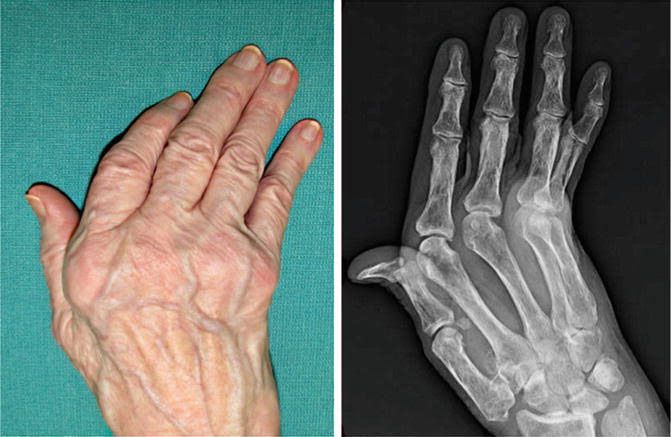

Rheumatiod Arthritis

Common findings in Rheumatoid arthritis include: Radial deciation of wrist. Ulnar deviation of fingers. Swan neck deformity of fingers. Boutonniere deformity of thumb.